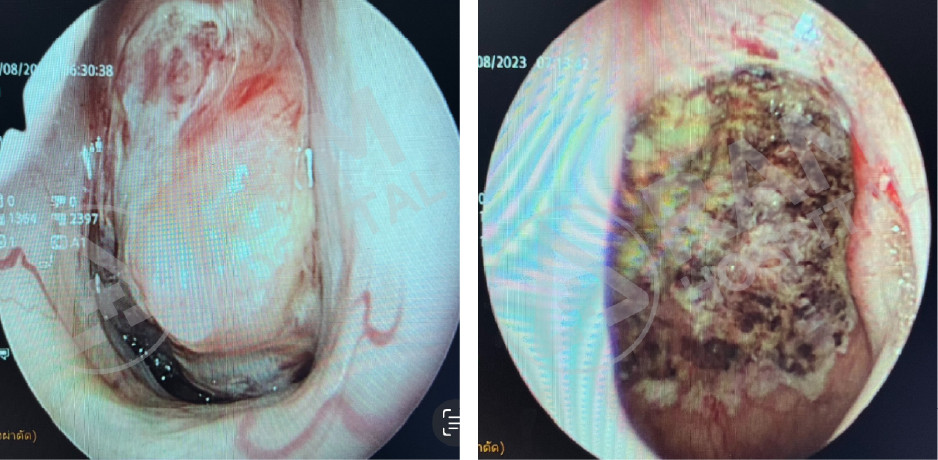

通过口腔内镜检查精准定位气道阻塞部位,并针对性地实施微创手术,以达到最佳治疗效果和最小创伤,核心技术包括:包括软腭手术联合颈部肌肉缝合收紧手术、借助口腔内镜缩小舌根的手术。

通过口腔内镜辅助,对舌根和会厌部位的肿瘤进行微创手术

通过口腔内镜辅助,对喉部或声带部位的肿瘤进行不用刀的微创手术。

术前 |

术后 |

术后

Source: Photo courtesy of Dr. Puripan Aramawattanapong, Ear, Nose, and Throat Specialist